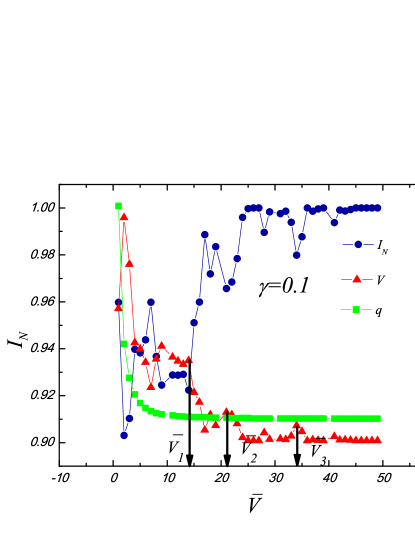

XI.1.2 Weighted graphs

In Figs. (6, 7), we provide the “multiresolution” results for the weighted graph (Eq. (2)) of and for the brain image. Both the resolution and the threshold control the hierarchy structures: the peaks in the normalized mutual information and variation of information always correspond to the jumps in the number of communities . The jumps in correlate with the changes in hierarchal structures on different scales. We can combine both parameters to obtain the desirable results in the test images. See, e.g., the plot of .

The results of our method with weighted edges are more sensitive to the changes of parameters (as seen from a comparison of Fig. 6 with Fig. 5). According to Eq. (2), edges with small (or large) difference will decrease (or increase) the energy by (or ). However, if the unweighted graphs and the Potts model with discrete weights (Eq. (1)) are applied, the edges with small or large “color” difference will decrease or increase the energy by the amount of or . Thus, considerable information (e.g., the “color” of each pixel) is omitted when using an unweighted graph approach.